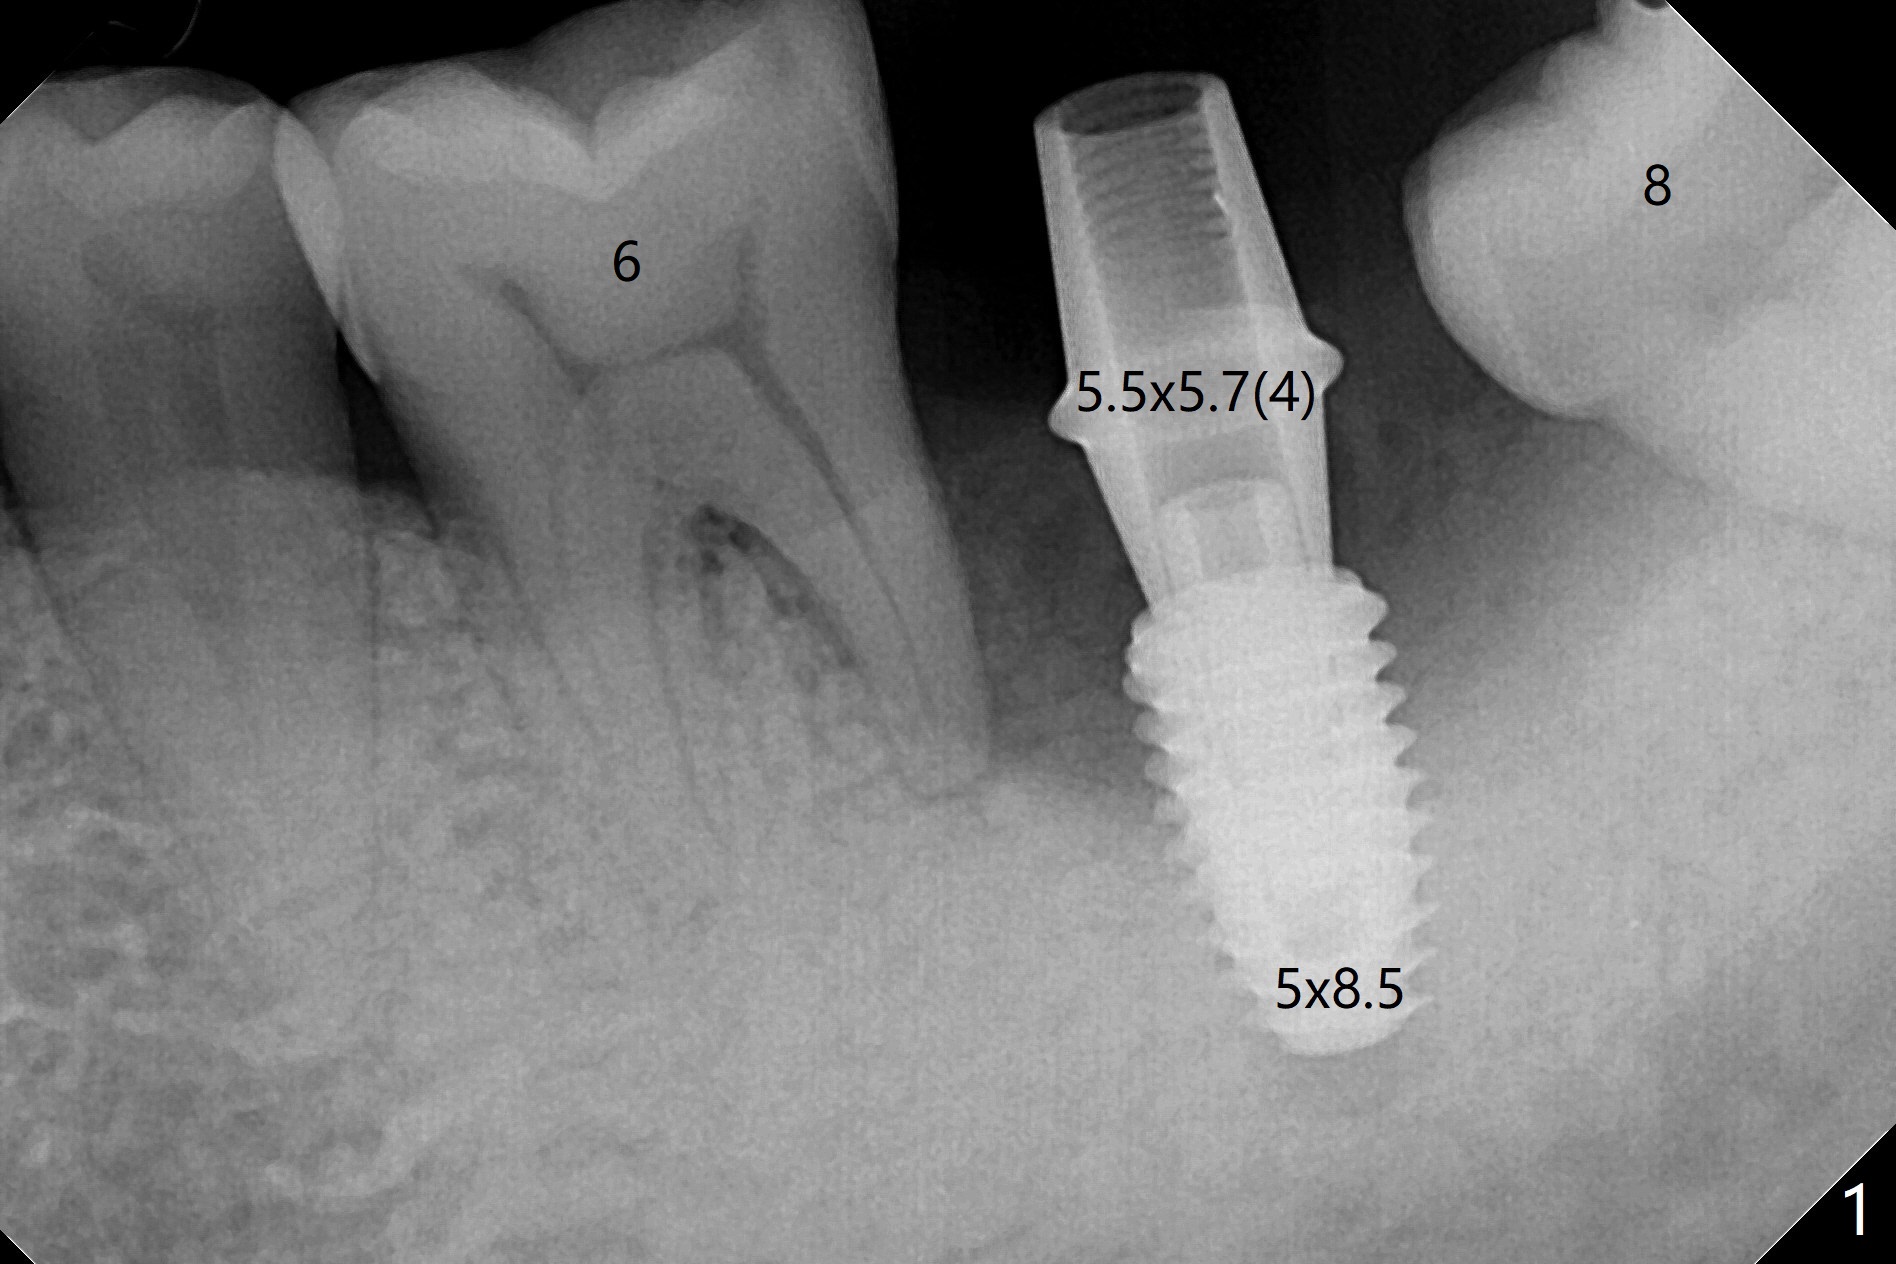

植骨成功必须有两个成分,软硬组织,牙龈提供血运和口袋,而硬组织防止骨粉塌陷。例如即刻植体和基台是可靠,免费(与钛网而言)硬性支撑,今天添加另外一个天然硬性支撑,那就是预后不是很好邻牙。40岁男左下7严重骨质吸收,颊侧,舌侧骨板缺失,骨粉(红色圆圈)将放置6远中,让它发挥余热。8暂时保留,这样7导板稳定些,植入更准确(图一),之后拔除8。结果术中改变计划,得寸进尺,也想保留8,理由骨粉更稳定(图二:*),尤其是远中。6,8牙根面做了刮治。为了证实基台完全就位,又拍摄一张咬翼片(图三),这时植体螺纹清晰。植体与基台之间有两个重要接触部分,第一,图三空箭头,两者必须完全融合(必须没有间隙),理论上可以形成冷焊接(cold welding);第二,短箭头,公母六角形(hex)相接,之间有间隙。如果初步稳定性低,选择愈合基台,与植体交接也必须有X光片验证,两者之间不应该有间隙。如果有间隙,愈合过程,愈合基台很可能脱落,造成病人不安,增加我们工作量,破坏临床进展。图三:术后即刻。术后5.5月(图四)骨粉丧失许多,牙冠外面使用牙周敷料或者直接使用树脂敷料,可能会减少骨粉流失。临床上智齿近中好像没有明显倒凹,取模,估计以后食物坎塞不会太严重。术后6月(牙冠粘固,拧紧25Ncm,图五),螺纹没有暴露。